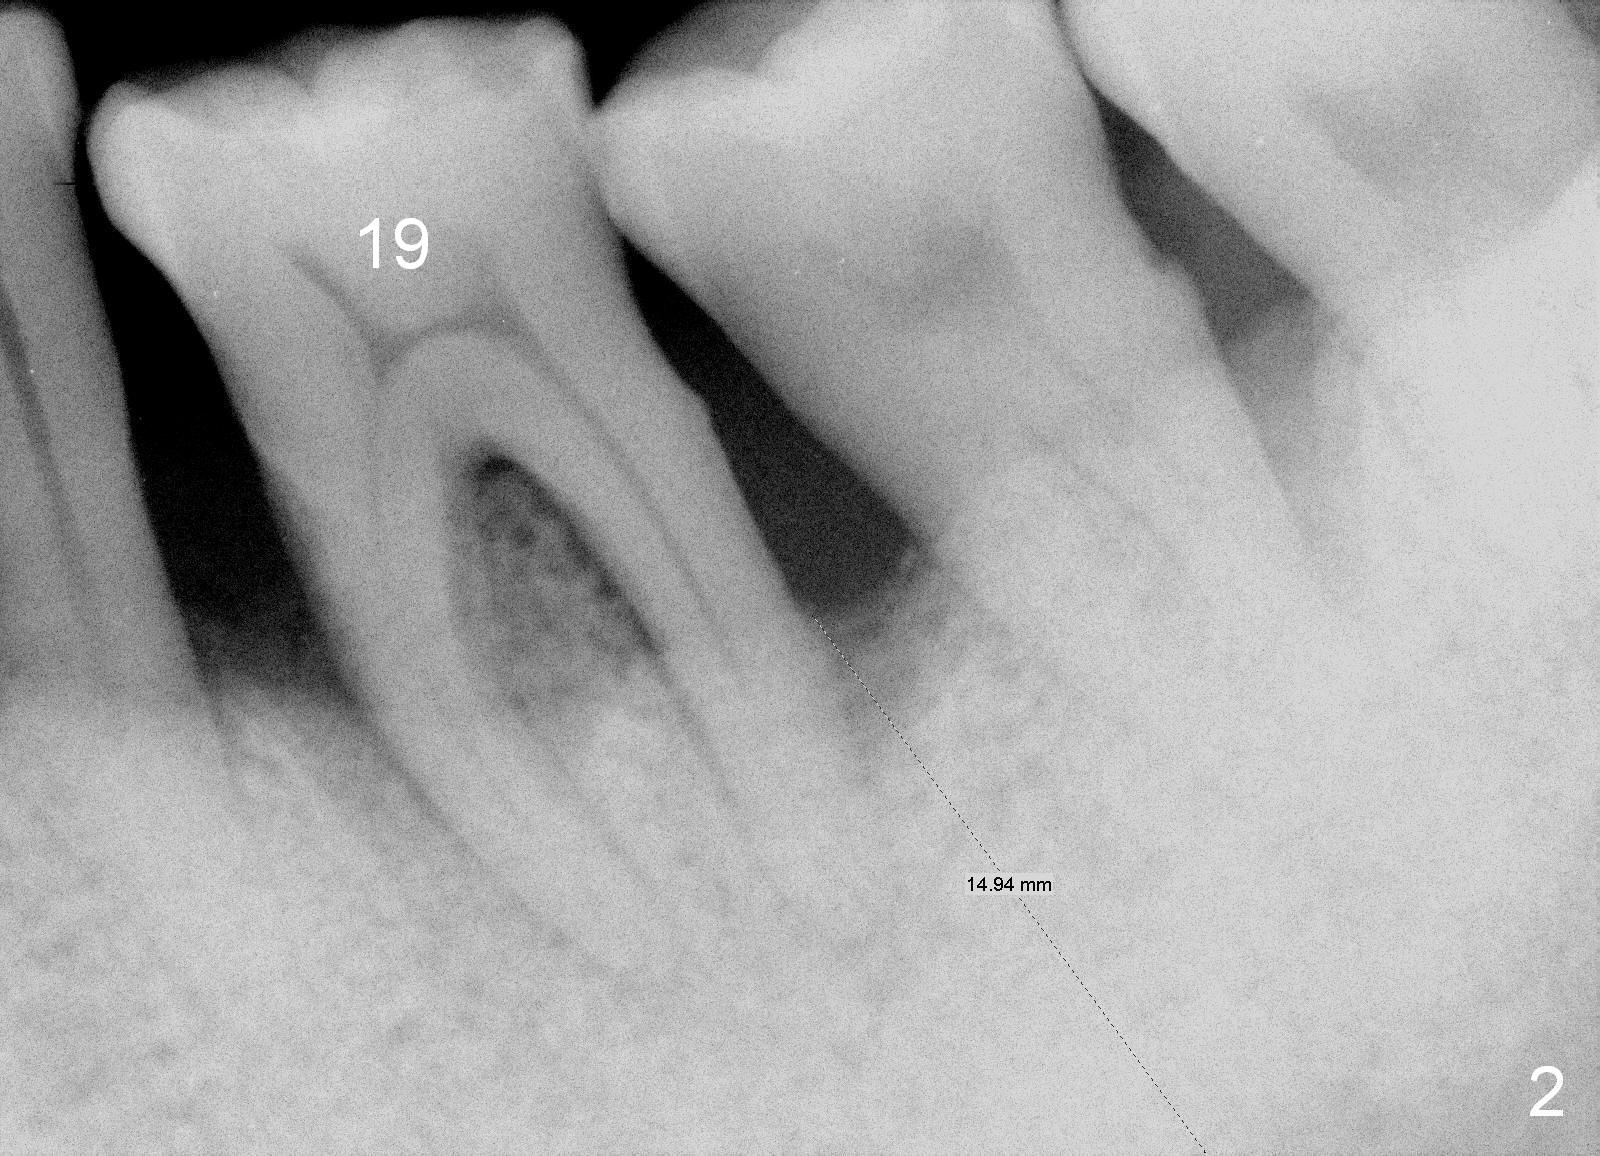

Osteotomy As Mesial As Possible

A 62-year-old man will return for #19 immediate implant (Fig.1,2). These X-ray films were taken 4.5 years ago. Chronic periodontitis has been getting worse since. He requests treatment because of mobility. It is assumed that there is more bone loss. Pack 2% Xylocaine/1:50,000 Epinephrine gauze in the socket for hemostasis and further debridement. Start osteotomy mesial to the septum if it is present, since there is tendency to place osteotomy too distally. It is difficult to correct it. Initial depth will be 10 mm. Use Tatum tap prior to placement of SM implant (5.3x10 mm). Bone density is high in this patient when the implants were placed in the lower anteriors and the upper right. In fact the bone is so dense that 2.5 mm reamer cannot remove bone.